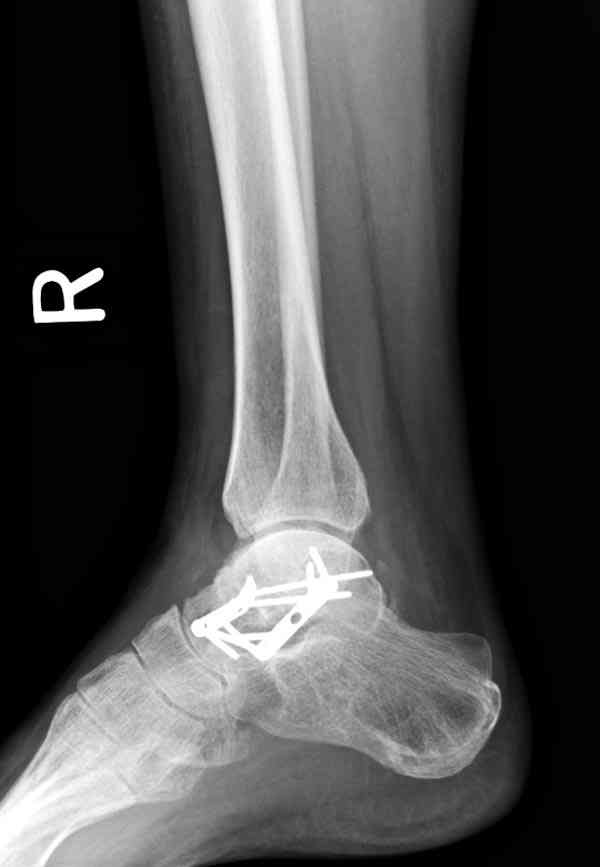

Случай с множественным оскольчатым переломом тарана оперированный из двойного доступа.

Через 2 мес.: